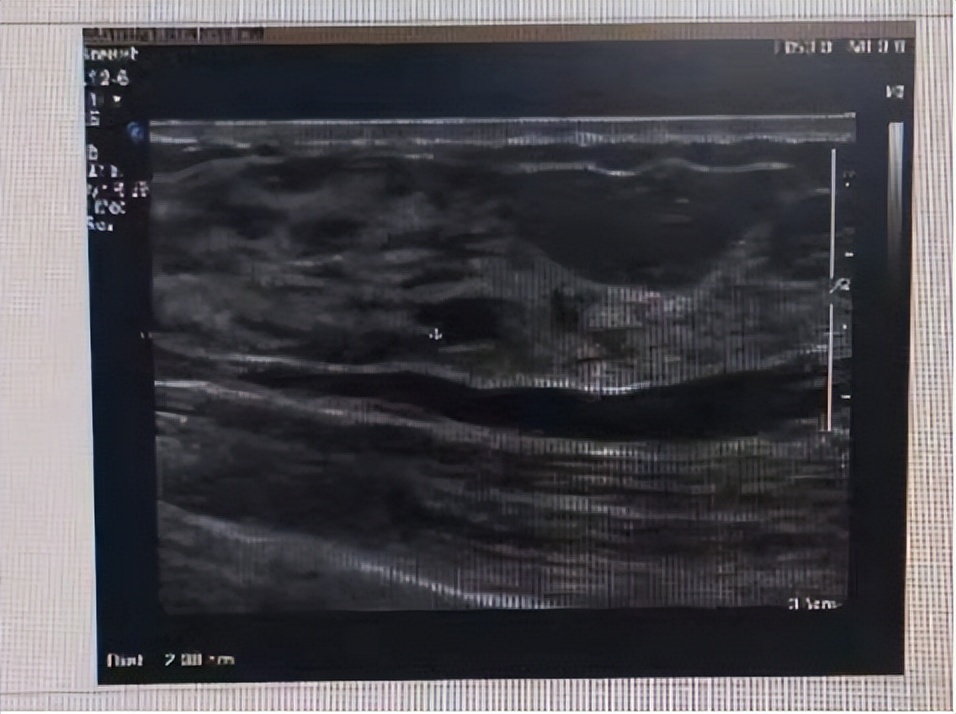

患者同意后,考虑到女性患者隐私部位的查体需要有其他女性在旁陪同,因此我叫来一名门诊护士,这名护士出现后,患者紧张的情绪缓解了许多。经查,患者双乳对称,双乳腺腺体不规则增厚,右乳未触及明显肿物,左乳有一包块,质韧,有压痛,双侧腋窝及锁骨上未触及明显肿大淋巴结,考虑乳腺增生可能性大。因此,在与患者沟通后,进一步完善了乳腺彩超,结果提示双乳腺增生,左乳结节(符合BI-RADS分级3类)。

对于这一结果,患者比较焦虑,担心3类是比较严重的情况,所以我对其进行了健康宣教,告知她3类指的是恶性危险性小于2%的肿块,可先观察,6个月后复查乳腺彩超,如有增大,再做进一步检查证实其性质,并进一步介绍了乳腺增生和乳腺癌的区别,患者焦虑情绪大大减轻,遂离院。